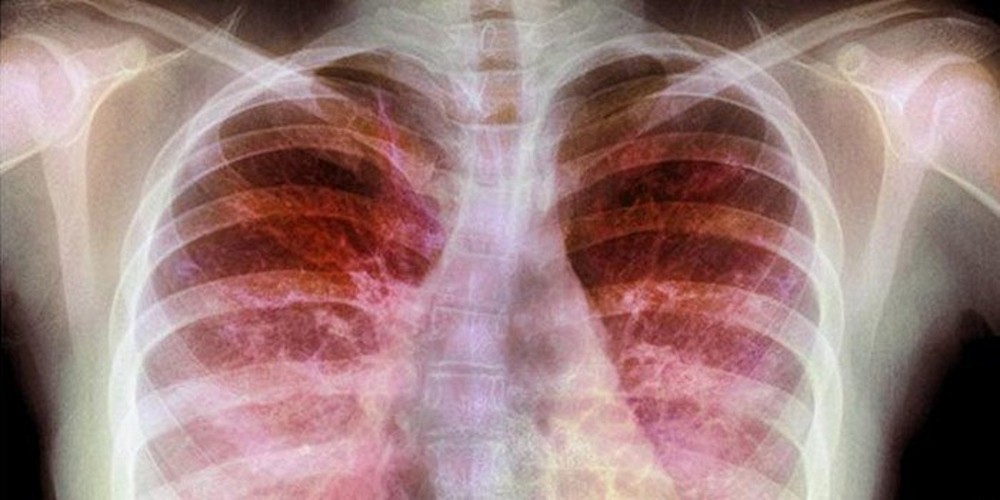

Existem diferenças no grau da mutação genética em cada paciente, então os sintomas podem variar, os mais comuns incluem pele salgada pela produção excessiva de cloro, tosse persistente e com muco, infecções pulmonares frequentes (pneumonia e bronquite), chiados no peito, falta de ar, fezes volumosas, desnutrição ou ganho de peso rápido e pólipo nasal.

Quando a doença ataca o sistema respiratório, por exemplo, o caso é melhorado a partir de cirurgias e medicamentos antibióticos, broncodilatadores e anti-inflamatórios. Também são recomendadas fisioterapia respiratória, atividades físicas e outras medidas multidisciplinares sempre com orientação médica.